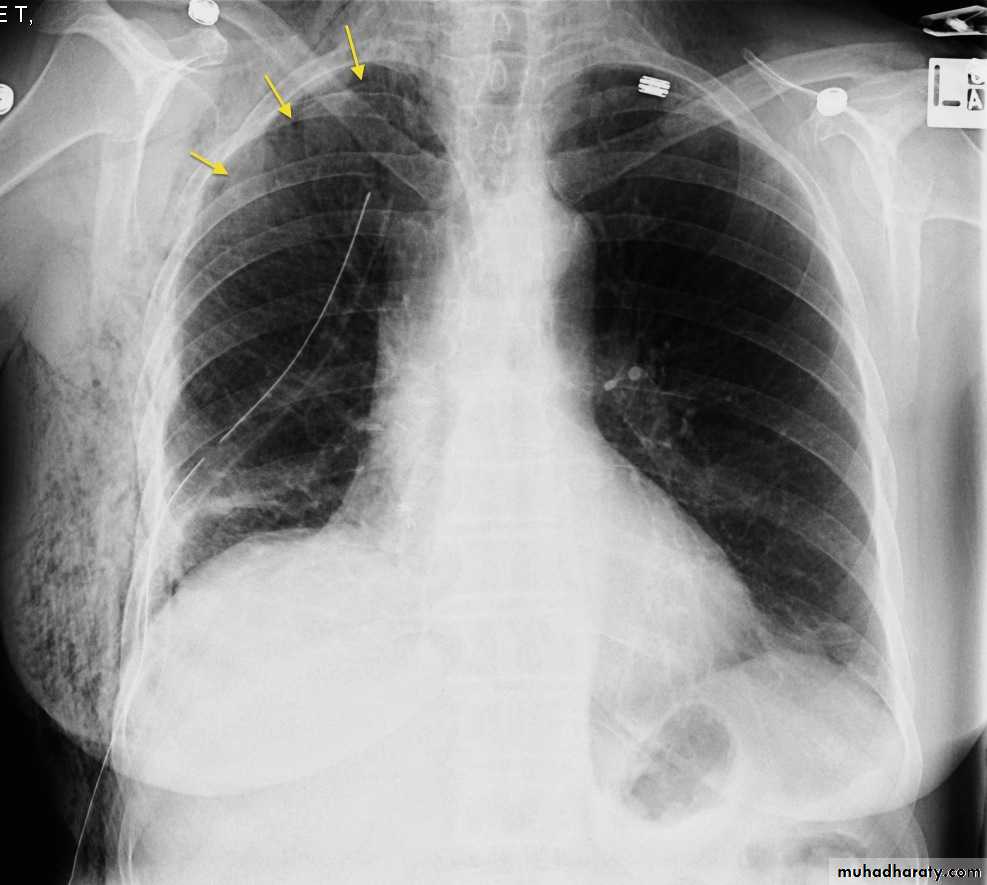

CXR:

Tension Pnenmothorax

What is the difference??Surgical Emphysema

CT scan

BronchoscopyPneumothorax